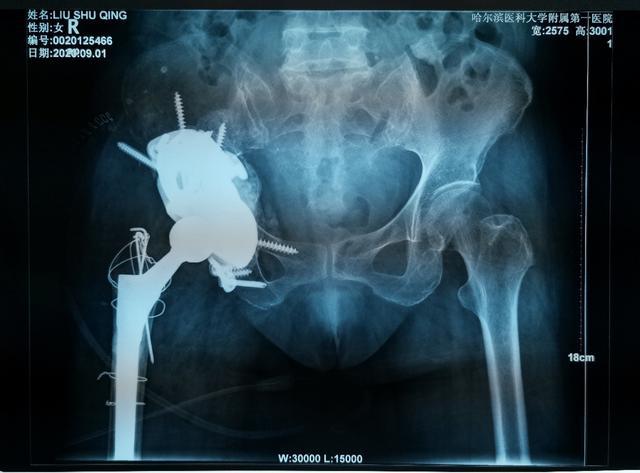

對于復(fù)雜髖關(guān)節(jié)翻修多為高齡患者,由于骨缺損巨大、骨質(zhì)疏松等因素,存在手術(shù)難度大、手術(shù)費用高等難題。近日,哈醫(yī)大一院骨科一病房3D打印團隊,應(yīng)用3D打印技術(shù),通過術(shù)前打印骨骼模型進行模擬假體安裝,成功為一名70歲,全髖關(guān)節(jié)置換術(shù)后15年,髖臼骨缺損巨大,髖臼上部坐骨、髂骨存在巨大空洞型缺損的患者實施了我省首例金屬3D打印三翼髖臼假體(Triflange)+股骨柄假體髖關(guān)節(jié)翻修術(shù),為患者更換了一個新的、穩(wěn)定的髖關(guān)節(jié)。目前患者已康復(fù)出院。

骨科一病房數(shù)字骨科負責(zé)人耿碩教授在詳細了解患者情況后,決定為患者進行個性化的金屬3D打印技術(shù)。定制化3D打印髖臼Triflange假體相比于傳統(tǒng)假體有以下優(yōu)點: 1、3D打印Triflange假體三個翼面通過螺釘分別固定在髂骨,恥骨和坐骨上提供了穩(wěn)定的初始固定。2、金屬3D打印擁有更好的孔隙率,有助于后期骨長入穩(wěn)定固定。3、個性化的術(shù)前設(shè)計,實現(xiàn)了墊塊和臼杯一體的輕量化支撐,更好地填充上方骨缺損重建髖關(guān)節(jié)的穩(wěn)定性,此外為應(yīng)對術(shù)中可能的意外情況,還可3D打印不同大小的墊塊。

為了確保手術(shù)順利,手術(shù)前,耿碩教授根據(jù)患者的影像數(shù)據(jù),經(jīng)過三維重建,真實復(fù)原了患者的右髖關(guān)節(jié)和盆骨模型。借助這一模型,耿碩教授可以全面精準(zhǔn)地了解患者的關(guān)節(jié)結(jié)構(gòu),骨質(zhì)情況等重要信息,為術(shù)前制訂精確地手術(shù)方案提供了重要的依據(jù)。手術(shù)當(dāng)日,耿碩教授手術(shù)團隊按照術(shù)前模擬,順利的將金屬假體精準(zhǔn)地安放在髖關(guān)節(jié)內(nèi)。經(jīng)過一周的康復(fù),患者已順利下地行走并康復(fù)出院。